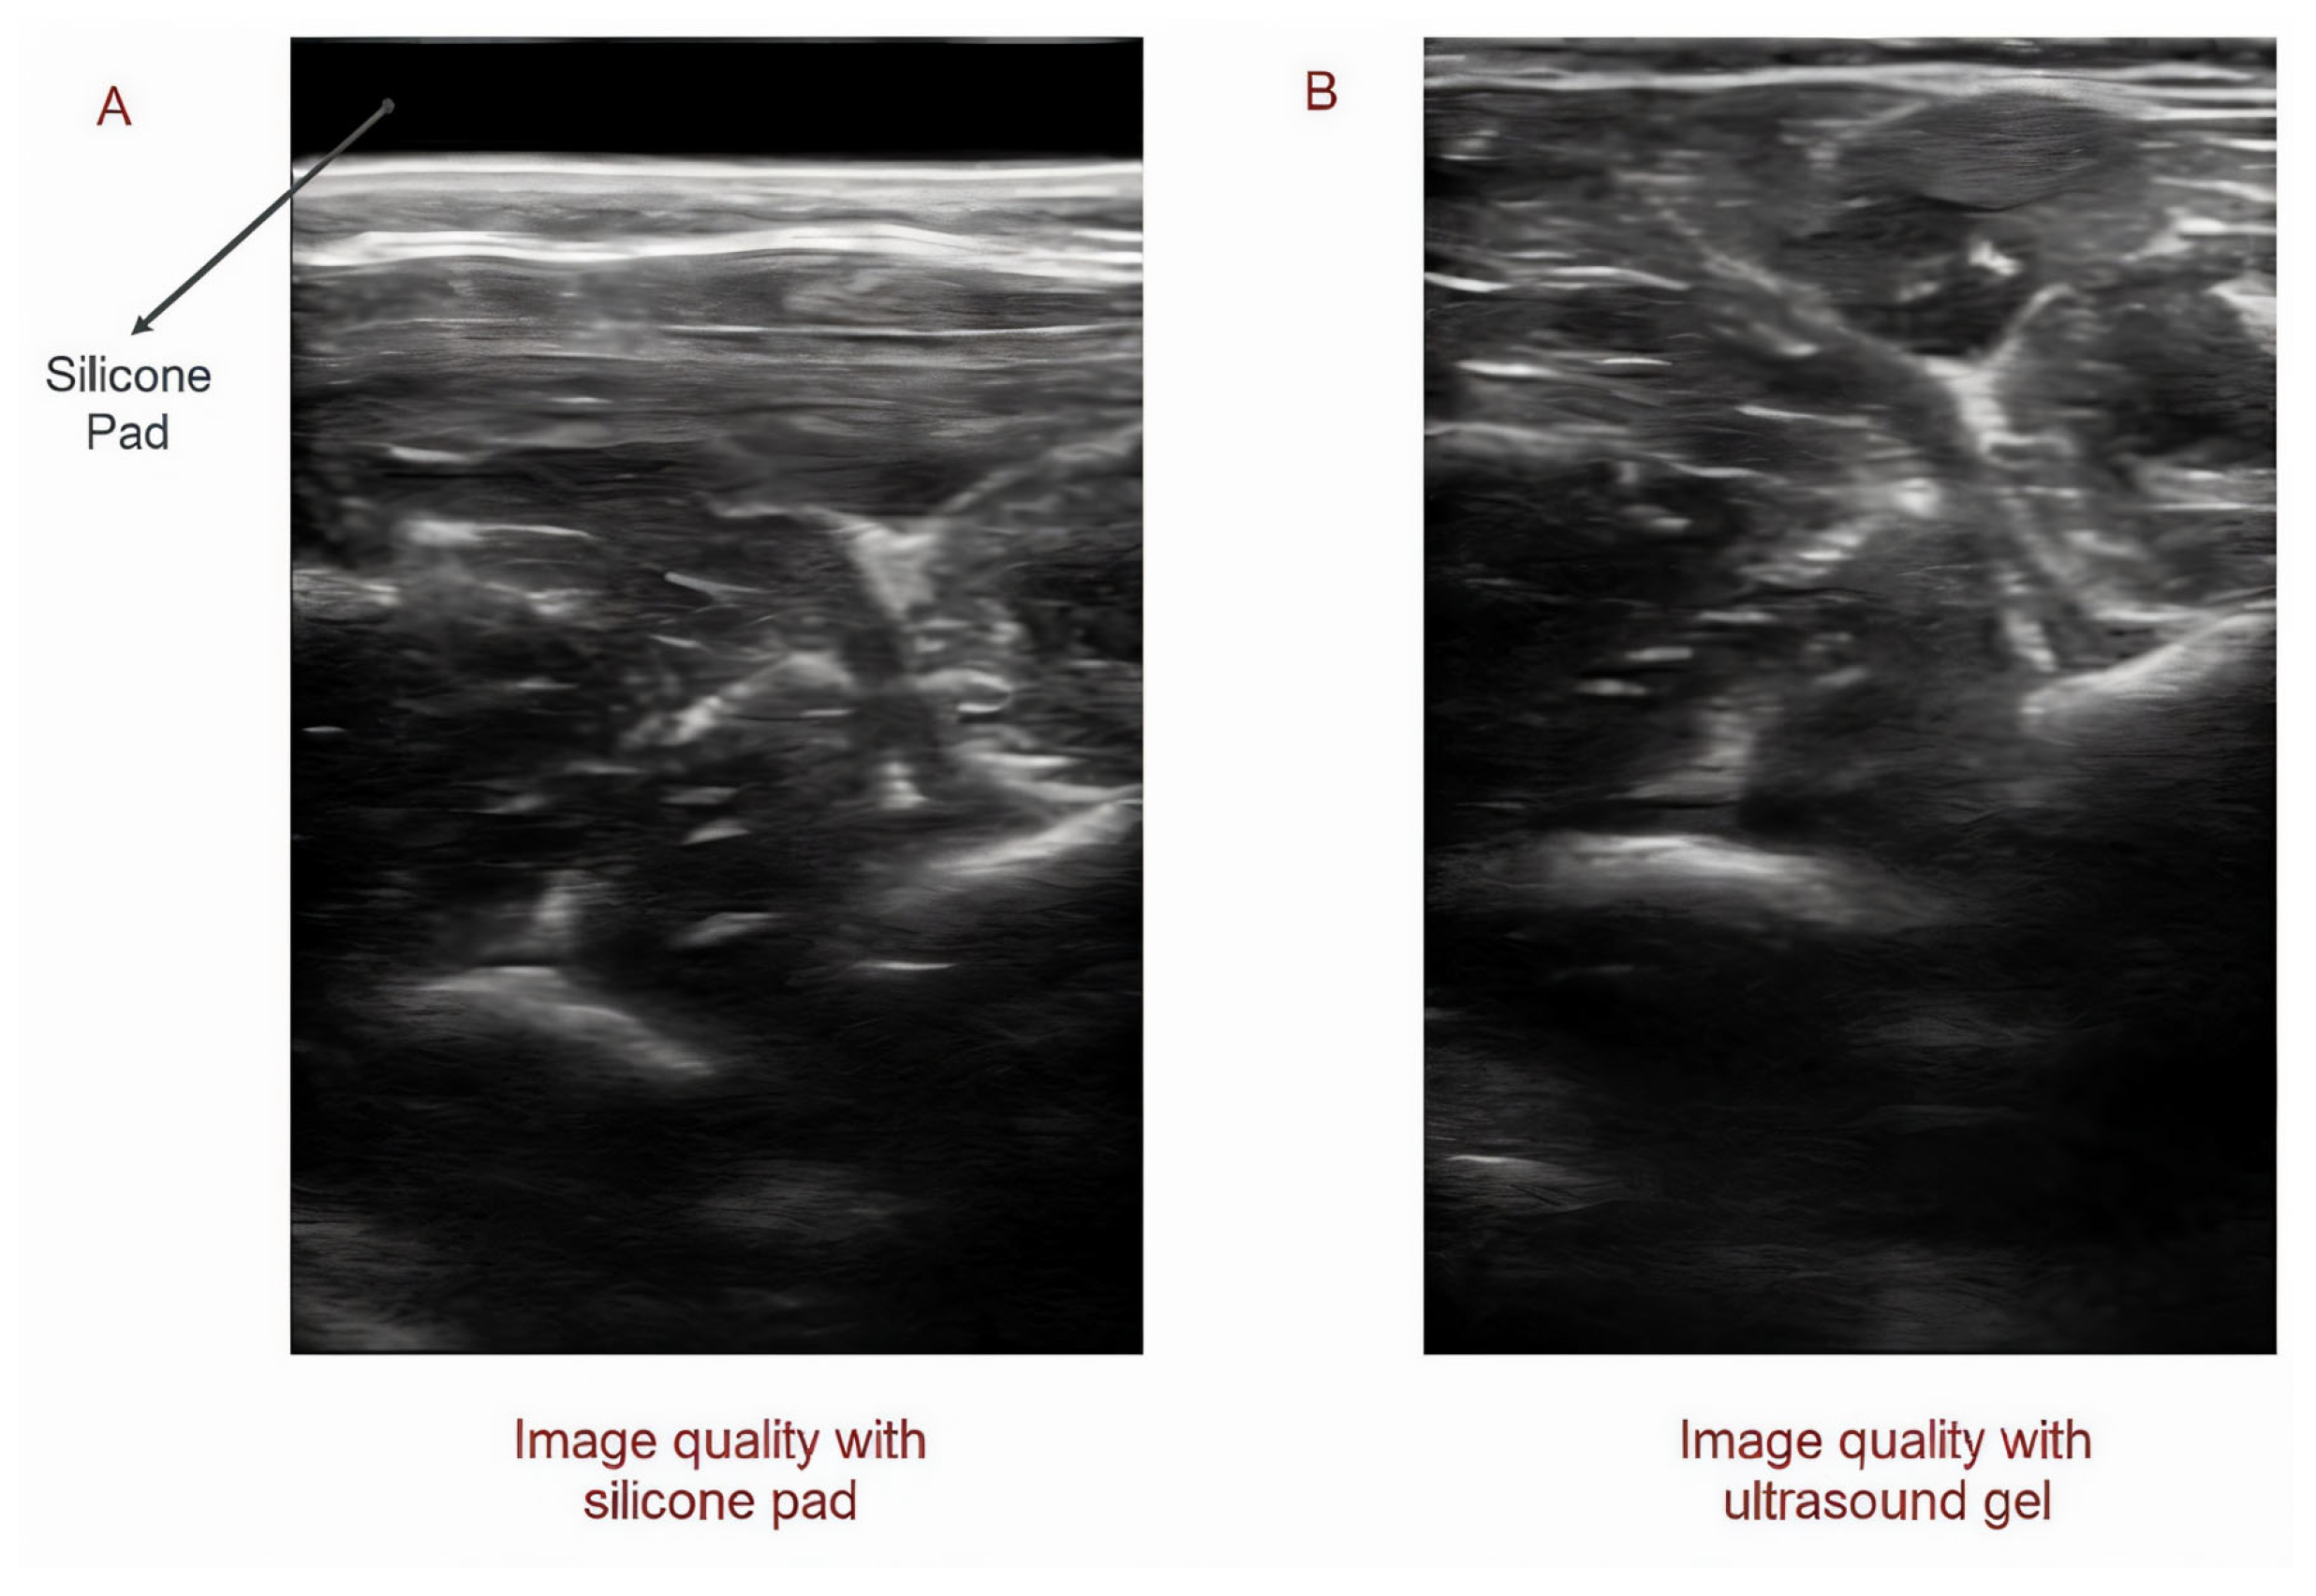

2.3. Replacing Ultrasound Gel and Gel Pad with Sticky Silicone Pad

Figure 3.

Utilizing silicone pad instead of ultrasound gel: Image quality using silicone pad (A) and ultrasound gel (B).

3.5.3. Evaluating the Potential of Using a Silicone Pad Instead of Ultrasound Gel or a Gel Pad

In the experiment conducted to evaluate the potential of the silicone pad to be replaced with ultrasound gel in order to control the prosthesis using ultrasound imaging, we observed that a silicone pad could provide real-time images of the muscle with good image quality and that the captured data could be utilized to enable real-time control over the prosthetic hand. Moreover, it was also discovered that the sticky silicon pad did not only stop transducer relocation but also reduced the stress on the skin by dampening the transducer’s reaction force.

In this study, we proposed the utilization of a biocompatible sticky silicone pad as an alternative to ultrasound gel. It was discovered that a silicone pad has the potential to be used instead of ultrasound gel or gel pads, avoiding skin contact with moisture and thereby serious skin problems. We also observed that sticky silicone pads can not only help to capture images from muscles with good resolutions but also, by increasing the friction between the transducer and the skin, prevent the relocation of the transducer, resulting in a decrease in misclassification in real-time control. In addition, during the offline test, the accuracy of hand gesture classification in the able-bodied group was around 99% when ultrasound gel was used to collect the data. However, when the ultrasound gel was replaced with a silicone pad, the accuracy increased to 100%.